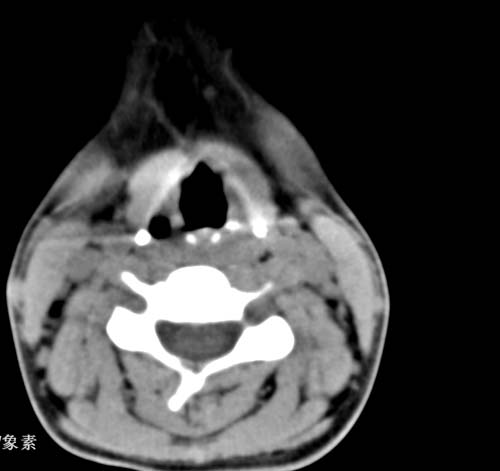

标题: CT22662:女 23 自述双侧颌下腺肿大年余 近来疼痛 左侧明显 [打印本页]

标题: CT22662:女 23 自述双侧颌下腺肿大年余 近来疼痛 左侧明显

见双侧颌下腺略肿大  未见结石及钙化 考虑双侧慢性炎症 ?请指教